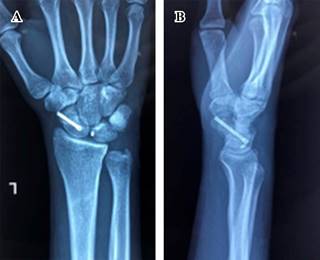

Masculino de 23 años de edad, sano, quien sufre caída del propio plano de sustentación contundiendo mano derecha con mecanismo de hiperflexión. Inicia con dolor, limitación funcional y edema importante en muñeca, motivo por el cual acude al servicio de urgencias. A la exploración física, llama la atención edema y deformidad en dorso de muñeca derecha con limitación funcional a expensas del dolor, sin alteraciones neurovasculares distales. Se realizan radiografías en proyecciones anteroposterior y oblicua de mano (Figura 1); se observa incongruencia entre líneas carpales con sospecha de fractura de escafoides. Se realiza tomografía computarizada (Figura 2), con la cual se completa diagnóstico de fractura luxación transescafo-perilunar.

Figura 1: Radiografías (A) anteroposterior y (B) oblicua de muñeca derecha. Se demuestra pérdida de las líneas de Gilula y fractura en escafoides.